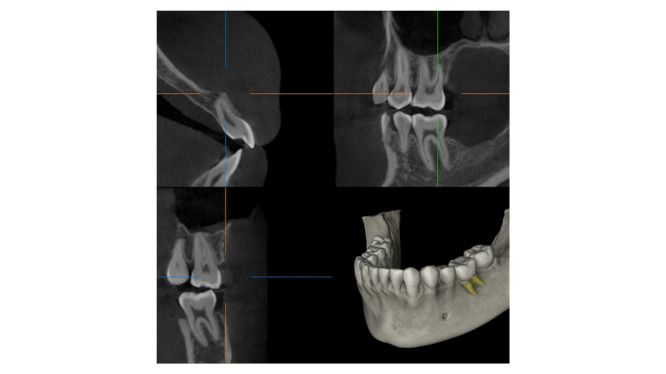

También, a diferencia de una imagen 2D, la tomografía Cone Beam genera una reconstrucción tridimensional del área estudiada, brindando acceso a cortes axiales, coronales y sagitales, además de modelos en 3D interactivos.

Con una sola toma de CBCT, se puede analizar:

- 🧠 El nervio dentario inferior y su cercanía a raíces de molares o al sitio de implante.

- 🫁 El seno maxilar, su altura, salud y neumatización.

- 🦴 Volumen y densidad ósea, clave para implantes o injertos.

- 🦷 Posición exacta de dientes retenidos, incluso con inclinaciones atípicas.

- ⚠️ Lesiones, quistes, reabsorciones o fracturas no visibles en radiografías tradicionales.

- 🧪 Espacios endodónticos, en tratamientos previos o planificaciones avanzadas.

Esta información, en conjunto, es lo que transforma la cirugía oral de una intervención exploratoria a un procedimiento predecible, controlado y seguro.